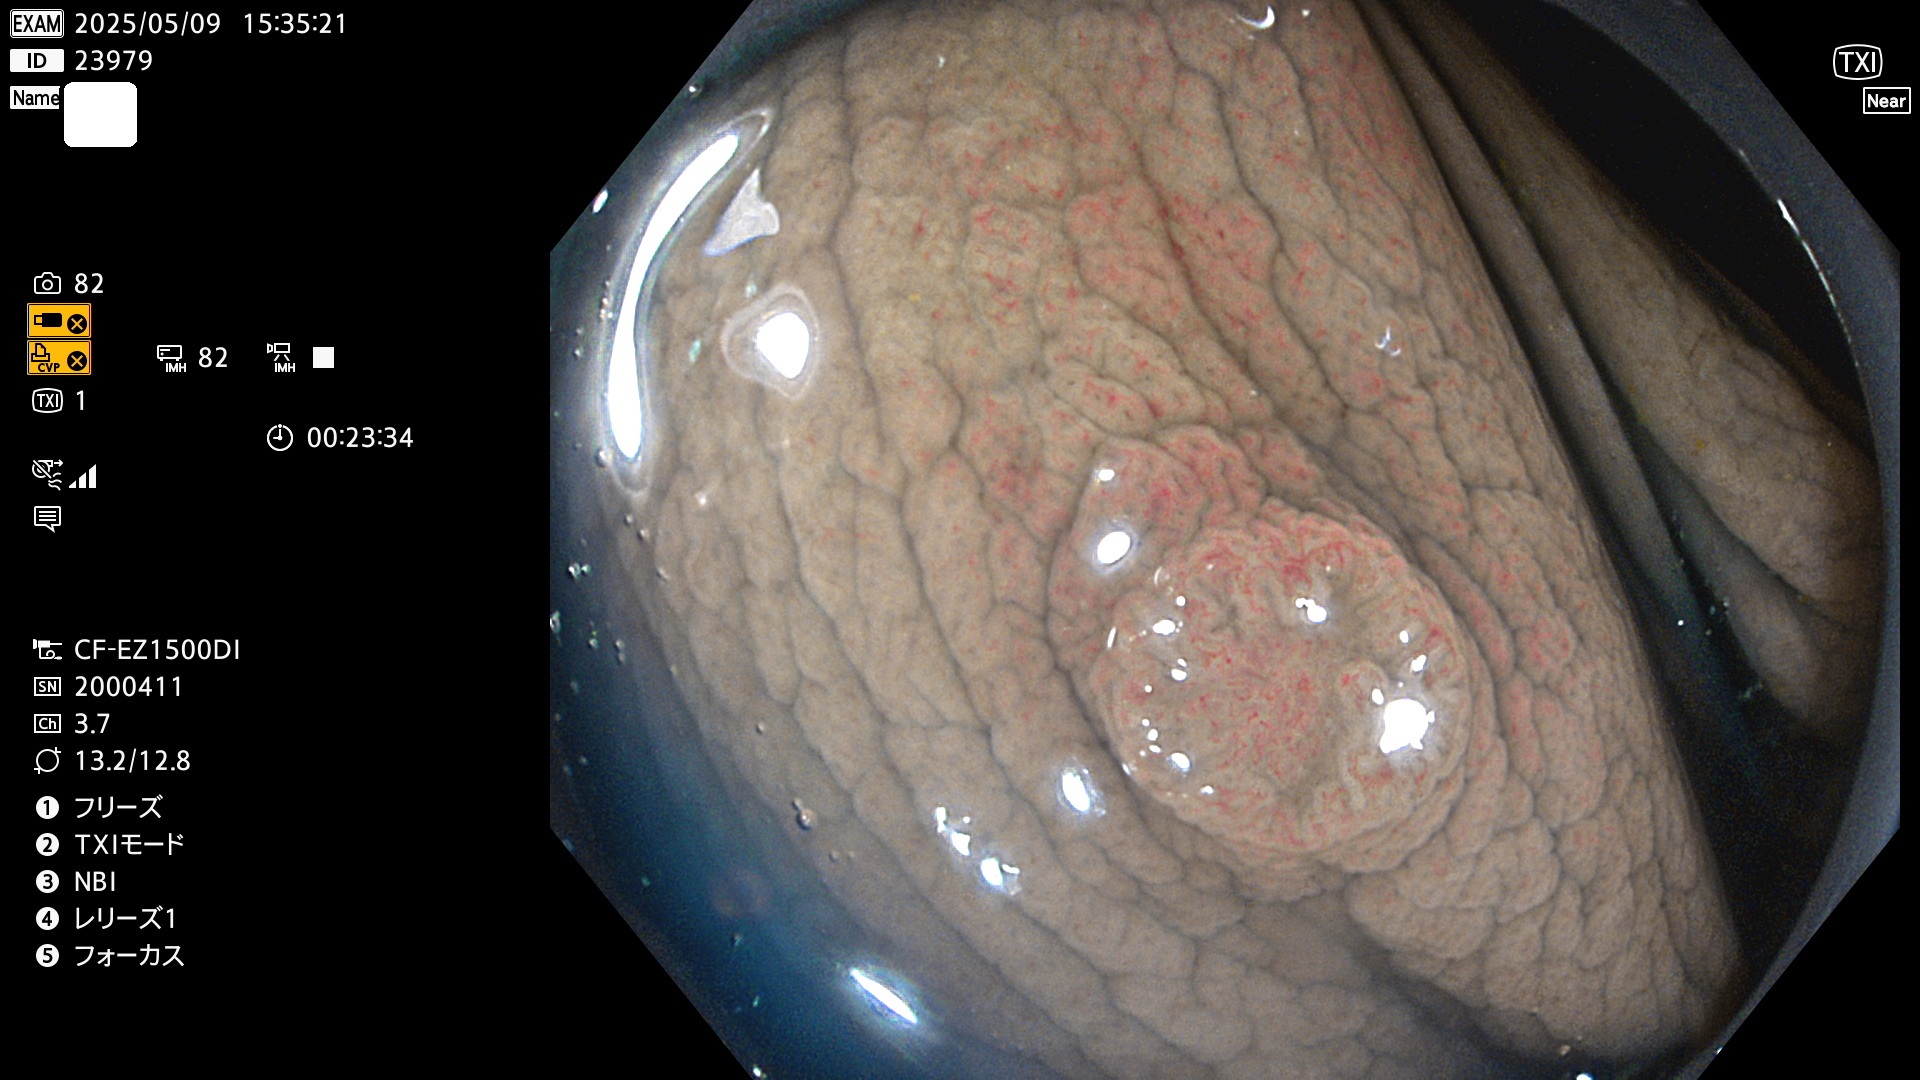

今週のUb、Uc型腺腫

完全に平坦な物をUb、陥凹している物をUcと呼びます。Ubは認識が困難で、Ucはびらん(炎症)と紛らわしいために見落とされやすく、「内視鏡後・大腸癌」の原因になります。

抽出の対象期間 2025年5月8日〜5月11日の4日間(48件の検査)14個 (14/48=29%)